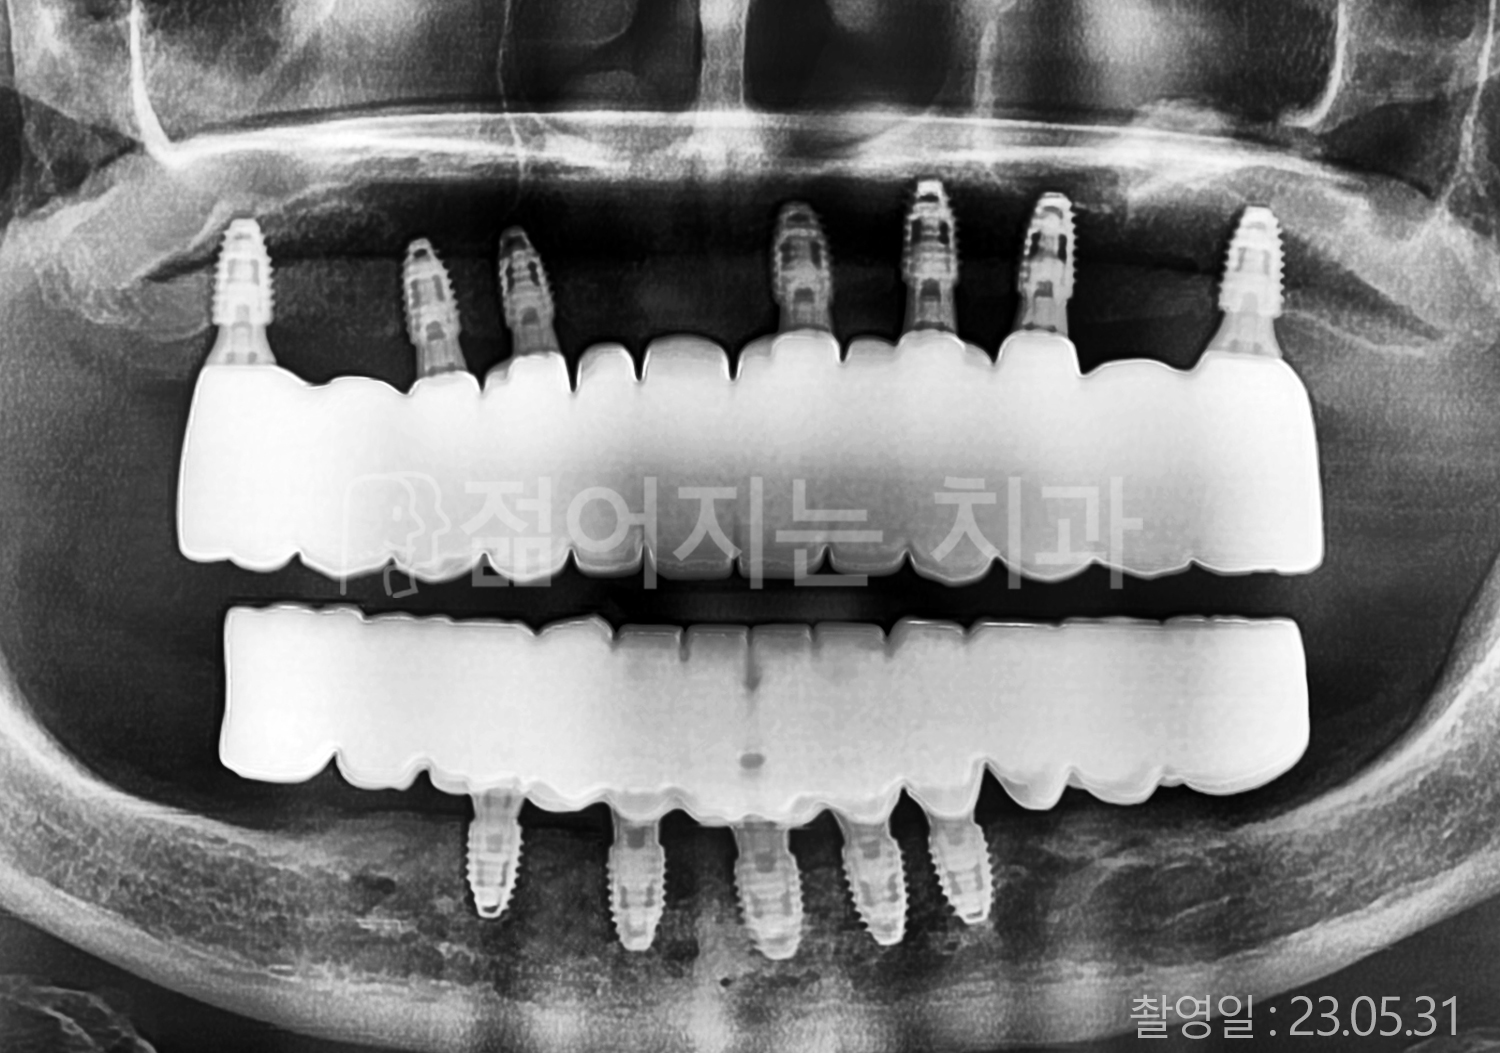

• 40대 전체치아 10개 이상 임플란트